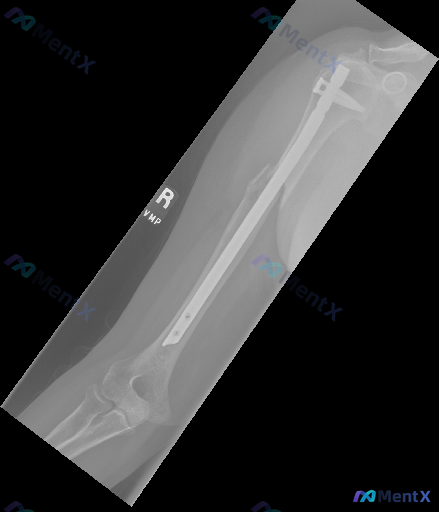

整理到一份右侧肱骨的X光正位片资料,是骨折髓内钉固定术后的复查。

- 髓内钉在位,近端、远端锁钉都在,位置还行,没看到明显断钉或松动

- 肱骨干中段有陈旧性骨折痕迹,骨折线已模糊,可见明显骨痂生长包裹断端

- 肩肘关节结构看着还好,没有明显的游离体或严重关节间隙问题

- 没有看到明确的广泛骨质疏松、局灶性溶骨/成骨破坏,也没有明显软组织肿胀

但这份资料里同时明确提示了一句「存在异常不规则现象」。

如果只看前半段可能会觉得是“愈合良好”的术后片,但加上这句提示之后,这个“骨痂”会不会其实不简单?